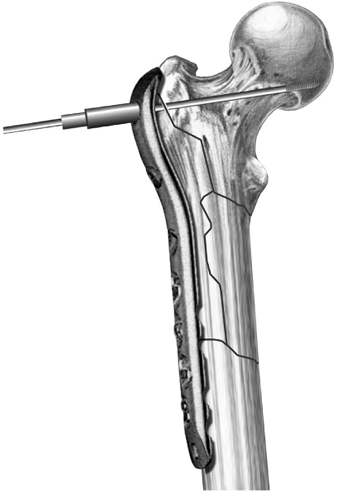

![]() |

Figure 19.15. A. Example of a locking plate for the treatment of a comminuted subtrochanteric fracture around a femoral head prosthesis. B.

The three proximal guide wires and screws are placed proximally, and the bone is reduced to the plate. An indirect reduction technique was employed in this case, followed by well-spaced locking screws along the shaft of the plate distally. C. X-rays at 3 months show maintained anatomic alignment of the fracture and evidence of healing. |